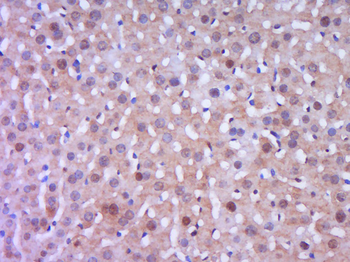

FC, ICC, IF, IHC-Fr, IHC-P, WB

Human, Mouse, Rat

Rat

Rabbit

Recombinant

Unconjugated

200 μl, 50 μl, 100 μl - Featured